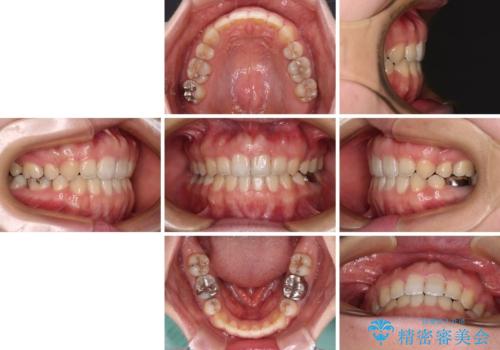

- 審美装置

- 2年4ヶ月

治療は順調に進み、予定された期間で終了することができました。

装置除去後には、スッキリとした口元となり、大変満足していただきました。